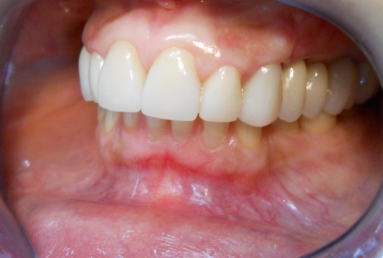

After treatment:

– zirconium/ceramic bridge in the lateral right maxillary area

– two implants and zirconium/ceramic bridge in the lateral left maxillary area

– full ceramic individual crowns in the frontal maxillary area, correcting at the same time the occlusion and the position of the frontal teeth.

– the lower arch was restored with a zirconium/ceramic bridge in the lateral right area and composite esthetic fillings + teeth whitening for the rest of the natural teeth.